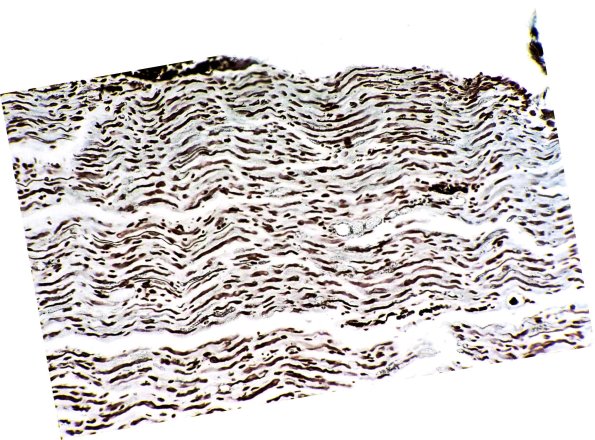

The dorsal and ventral spinal roots in longitudinal section showed patchy loss of myelin (LFB-PAS, 9A1) with relative preservation of axons (Bodian, 9A2)